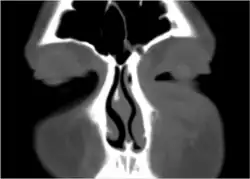

Marked left facial edema due to periorbital cellulitis following a dental procedure.